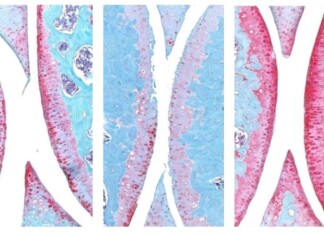

Anti-Aging Drug Regrows Knee Cartilage in Major Breakthrough That Could End Knee Replacements